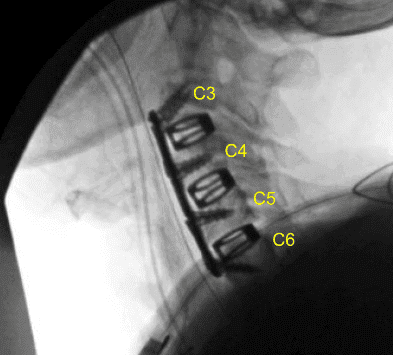

We measured out our anterior plate, placed it over our levels of interest, and pinned it into place. We obtained x-rays, and then applied the screws as listed above. We locked all the screws in place and obtained final AP and lateral x-rays.